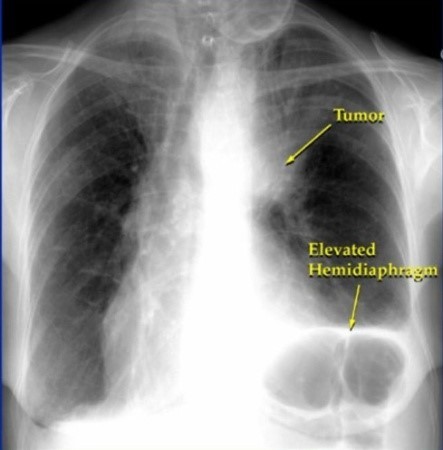

폐렴 증상 폐렴은 폐의 세균, 바이러스, 곰팡이 등 감염으로 인해

폐포(폐 속의 공기 주머니)에 염증이 생기고, 고름이나 액체가 차는 질환입니다.